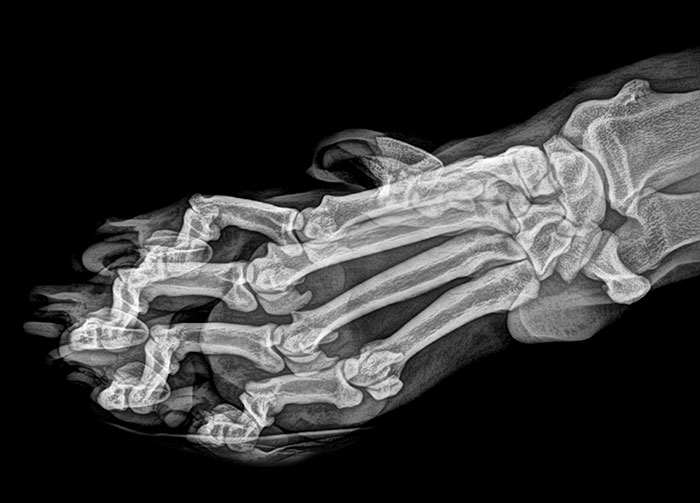

Advanced Rheumatoid Arthritis

My daughter was diagnosed with RA when she was 13. She is 29 now and has had three surgeries to improve her joints to help her be able to walk. Her toes looked much like this X-ray. This is a horrible illness that is invisible until it is at this point. The pain that these patients deal with every day is heartbreaking. People still give her dirty looks when she uses a handicap parking space. Imagine if your toes looked like this...don't you think you would want to walk as little as possible?

The Worst Case Of Rheumatoid Arthritis I've Ever Seen